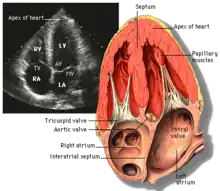

Apical four chamber (A4C)

Apical 4 chamber

This view is obtained at the apex of the heart and looking toward the base of the heart (where the valves are). In this view, the mitral valve, tricuspid valve, and all four chambers are visible. This view shows the right ventricle from base to apex and is a useful view to estimate RV systolic function. TAPSE (= tricuspid annular plane systolic excursion) is also measured in this view with M-mode through the lateral tricuspid annulus.

Structures:

• Inferior septum and anterior lateral segments of the left ventricle

• Right ventricle

• Left atrium

• Right atrium

• Mitral valve

• Tricuspid valve

Measurements in this view can be used to quantify the heart:

• RV size and function; TAPSE

• Left atrial size

• Right atrial size

• Mitral valve flow is best seen in this view and has the best angle with probe to estimate flows

• Tricuspid valve flow

• Tissue doppler at the mitral valve annulus (septum and lateral wall) for diastolic function

• Agitated saline bubble study for right to left shunting (PFO, ASD, VSD)

• With contrast, apical and mural LV thrombi can be easily seen